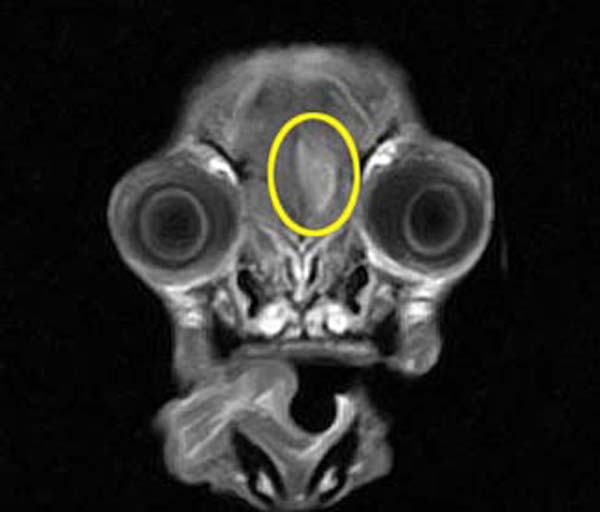

痙攣発作の原因を調べるためにMRI検査を行いました。検査の結果、頭蓋内軸外腫瘍(髄膜腫や組織球性肉腫)などを第一に疑い、飼い主様とのご相談の結果抗てんかん薬と抗がん剤による内科治療となりました。